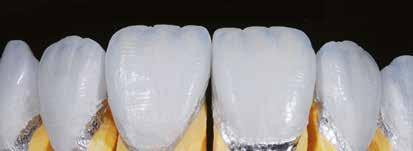

A cikkünkben bemutatásra kerülő eset ellátása során preparációt héjak készre vitele során a platinafólia technikát alkalmaztuk.

kívül vékonyak, és ezáltal a végleges rögzítésük előtt jelentős olyan minimál invazív kezelési eljárásnak számítanak, amely

elérni. A fent leírtak alapján bátran

preparációt nem igénylő héjak készítése mellett döntöttünk. A alkalmaztuk. Annak ellenére, hogy az elkészítésre kerülő héjak rendjelentős törésveszéllyel állunk szemben, összességében mégis amely segítségével kifogástalan esztétikai eredményeket lehet javasoljuk e módszer alkalmazását.

A fogászati kezelések során manapság már nem kizárólag az esztétikai megjelenés helyreállítására törekszünk. Sokszor a kedvezőtlen esztétikai megjelenés hátterében álló okok következményes módon a fogazat funkcionális működését is károsítják, így a kezelések során ezeknek a helyreállításával is foglalkoznunk kell. A különböző funkcionális és esztétikai diszkrepanciák kezelésére számtalan módszer létezik, ám ezen fogászati beavatkozások mindegyikében közös, hogy a kivitelezésük során nagyon szoros együttműködésre van szükség a kezelést végző fogorvos és a munkáját segítő fogtechnikus között. Az alábbi esetbemutatás során egy fiatal hölgypáciens fogazatának héjak alkalmazásával történő esztétikai és funkcionális rehabilitációját szeretnénk ismertetni.

Esetbemutatás

A 19 éves hölgypáciens azzal a kéréssel jelentkezett a rendelőnkbe, hogy szebb fogakat szeretne. Az első konzultáció alkalmával megkérdeztük, hogy mi zavarja leginkább a fogazatának jelenlegi megjelenésében, valamint azt is megbeszéltük vele, hogy milyen végeredmény elérése esetén lenne maradéktalanul elégedett. Ebben az esetben a kezelési célokat az alábbiakban határoztuk meg:

A páciens fogazata esztétikai megjelenésének és funkcionális működésének a lehető legtöbb, saját foganyag megtartása mellett történő helyreállítása (1. és 3. ábra). A lehető legideálisabb esztétikai végeredmény elérése érdekében néhány esetben a fogak alakjának módosítá -

sára is szükség van (2. és 4. ábra).